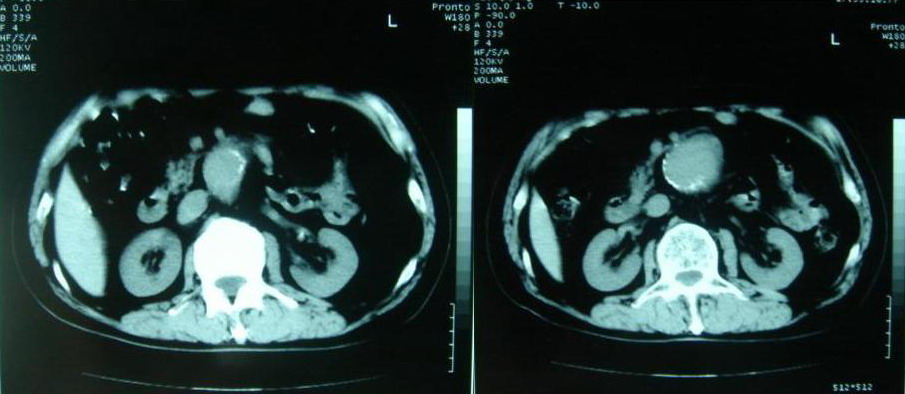

以下是引用zjzjr在2007-8-29 17:09:00的发言:[br]典型腹主动脉瘤累及双侧髂总动脉,建议增强扫描.

以下是引用why7912在2007-8-29 19:08:00的发言:[br]典型夹层动脉瘤,可见真假双腔及附壁血栓

以下是引用借我一双慧眼在2007-8-29 16:24:00的发言:[br]典型腹主动脉瘤累及双侧髂总动脉

以下是引用快乐男生在2007-8-29 16:45:00的发言:[br]腹主动脉及右髂总动脉大范围的管径增粗,[br]管壁多发的钙化,[br]并见真假腔(双腔征),假腔可见附壁血栓.[br]考虑腹主动脉夹层动脉瘤 .建议增强或mri